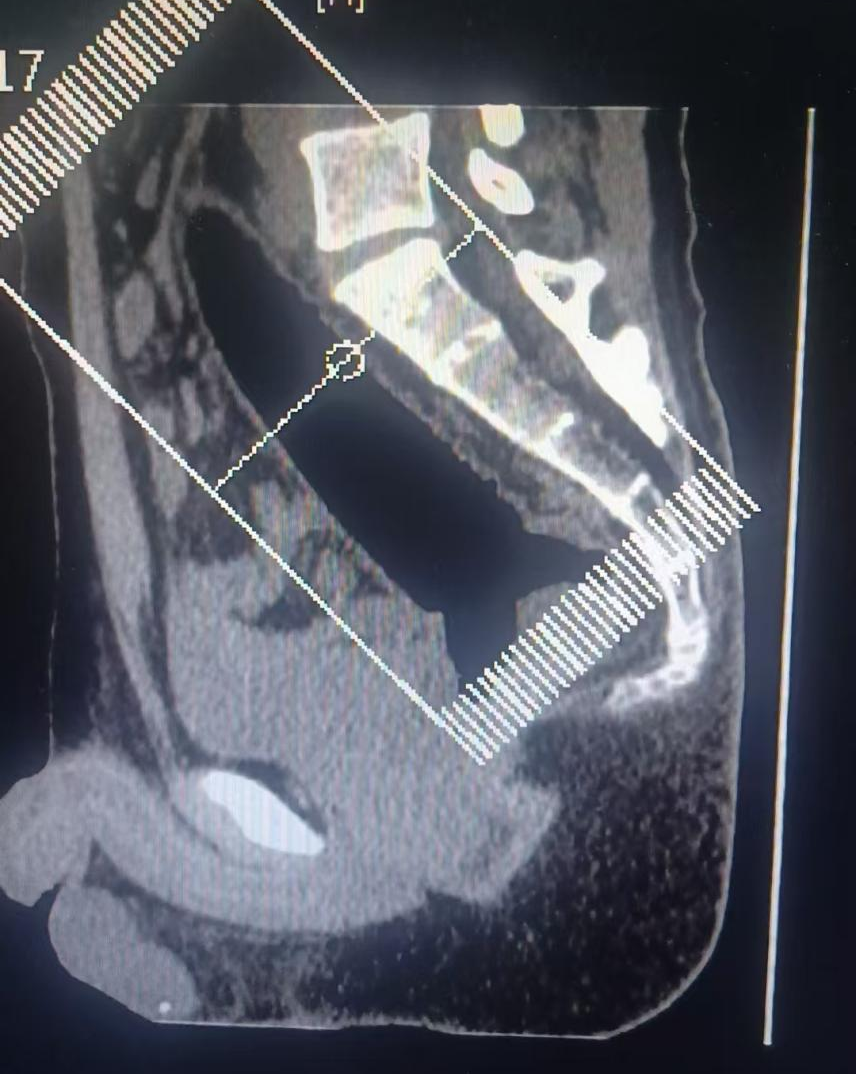

问诊时,小陈含糊提及异物是个“玩具”,不慎滑入肛门,医生指诊发现肛门内有明显异物,但已完全“吞没”,肉眼无法判断形态,DR检查仅见稍高密度影。追问后才知异物是透明硅胶材质,这才导致X光无法清晰照射出异物形状。

郑州人民医院普通外七科(肛肠)主任张胜威评估后表示:“异物已深入直肠,自然排出绝无可能,拖延可能导致肠梗阻、肠穿孔!”紧急手术后,在腰麻加持下,医生借助手术器械小心翼翼将这根22厘米长、3.2厘米粗的硅胶棒完整取出,现场医护都惊呆